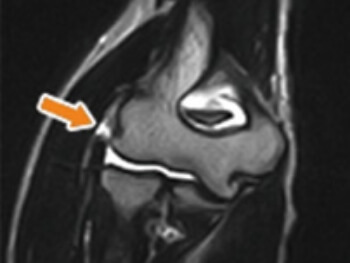

MRIでは、左の画像、矢印の部分のように、腱の断裂している部分が白く写ります。

テニス肘1

テニス肘2

丸で囲った部分が断裂部分です。 数ミリ程度の穴から肘の関節内に関節鏡を入れて、損傷部位を処置します。

多くの場合、腱の断裂部位がはっきりと見えます。